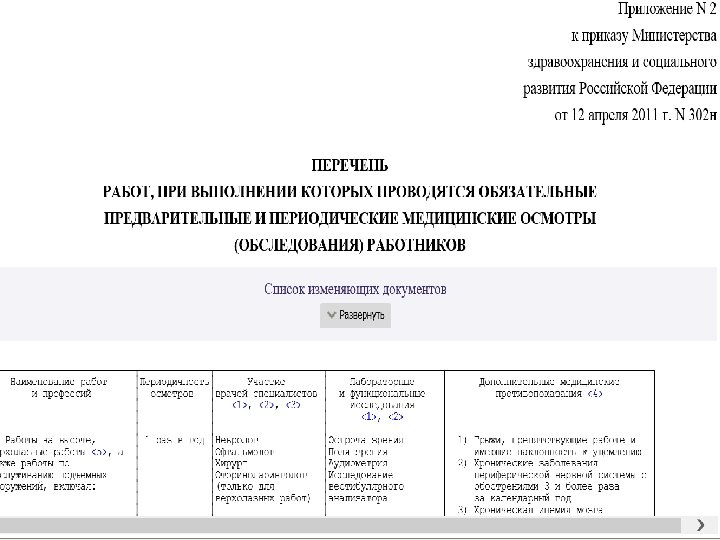

Приказ Минздравсоцразвития России от 12. 04. 2011 г. № 302 н «Об утверждении перечней вредных и (или) опасных производственных факторов и работ, при выполнении которых проводятся обязательные предварительные и периодические медицинские осмотры (обследования), и порядка проведения обязательных предварительных и периодических медицинских осмотров (обследований) работников, занятых на тяжелых работах и на работах с вредными и (или) опасными условиями труда» Утвердить: перечень вредных и (или) опасных производственных факторов, при наличии которых проводятся обязательные предварительные и периодические медицинские осмотры (обследования), согласно приложению N 1; перечень работ, при выполнении которых проводятся обязательные предварительные и периодические медицинские осмотры (обследования) работников, согласно приложению N 2; порядок проведения обязательных предварительных (при поступлении на работу) и периодических медицинских осмотров (обследований) работников, занятых на тяжелых работах и на работах с вредными и (или) опасными условиями труда, согласно приложению N 3.

Приказ Минздравсоцразвития России от 12. 04. 2011 г. № 302 н «Об утверждении перечней вредных и (или) опасных производственных факторов и работ, при выполнении которых проводятся обязательные предварительные и периодические медицинские осмотры (обследования), и порядка проведения обязательных предварительных и периодических медицинских осмотров (обследований) работников, занятых на тяжелых работах и на работах с вредными и (или) опасными условиями труда» Утвердить: перечень вредных и (или) опасных производственных факторов, при наличии которых проводятся обязательные предварительные и периодические медицинские осмотры (обследования), согласно приложению N 1; перечень работ, при выполнении которых проводятся обязательные предварительные и периодические медицинские осмотры (обследования) работников, согласно приложению N 2; порядок проведения обязательных предварительных (при поступлении на работу) и периодических медицинских осмотров (обследований) работников, занятых на тяжелых работах и на работах с вредными и (или) опасными условиями труда, согласно приложению N 3.